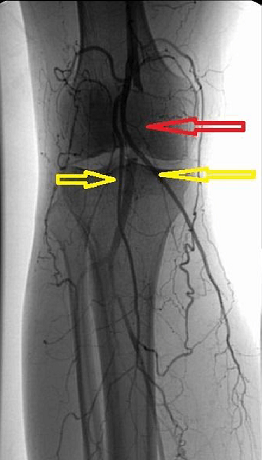

“间接恢复”是一种保守治疗的方法,是应用快走等肢体锻炼方法(图四)和扩张血管药物使堵塞血管旁的侧枝循环建立,通过这些开放的侧枝循环向远端组织供血。相当于“高速公路”发生堵塞后,在其周围开放多条小路,让血液通过这些小路到达远端组织(图五)。这种治疗方法起效慢,并且需要长期坚持,但效果可靠,比较适合症状轻微或者身体条件差不耐受手术的患者,它同样也是“直接恢复”和“旁路恢复”的辅助治疗手段。

▲ 图五 闭塞动脉周围形成的侧枝循环